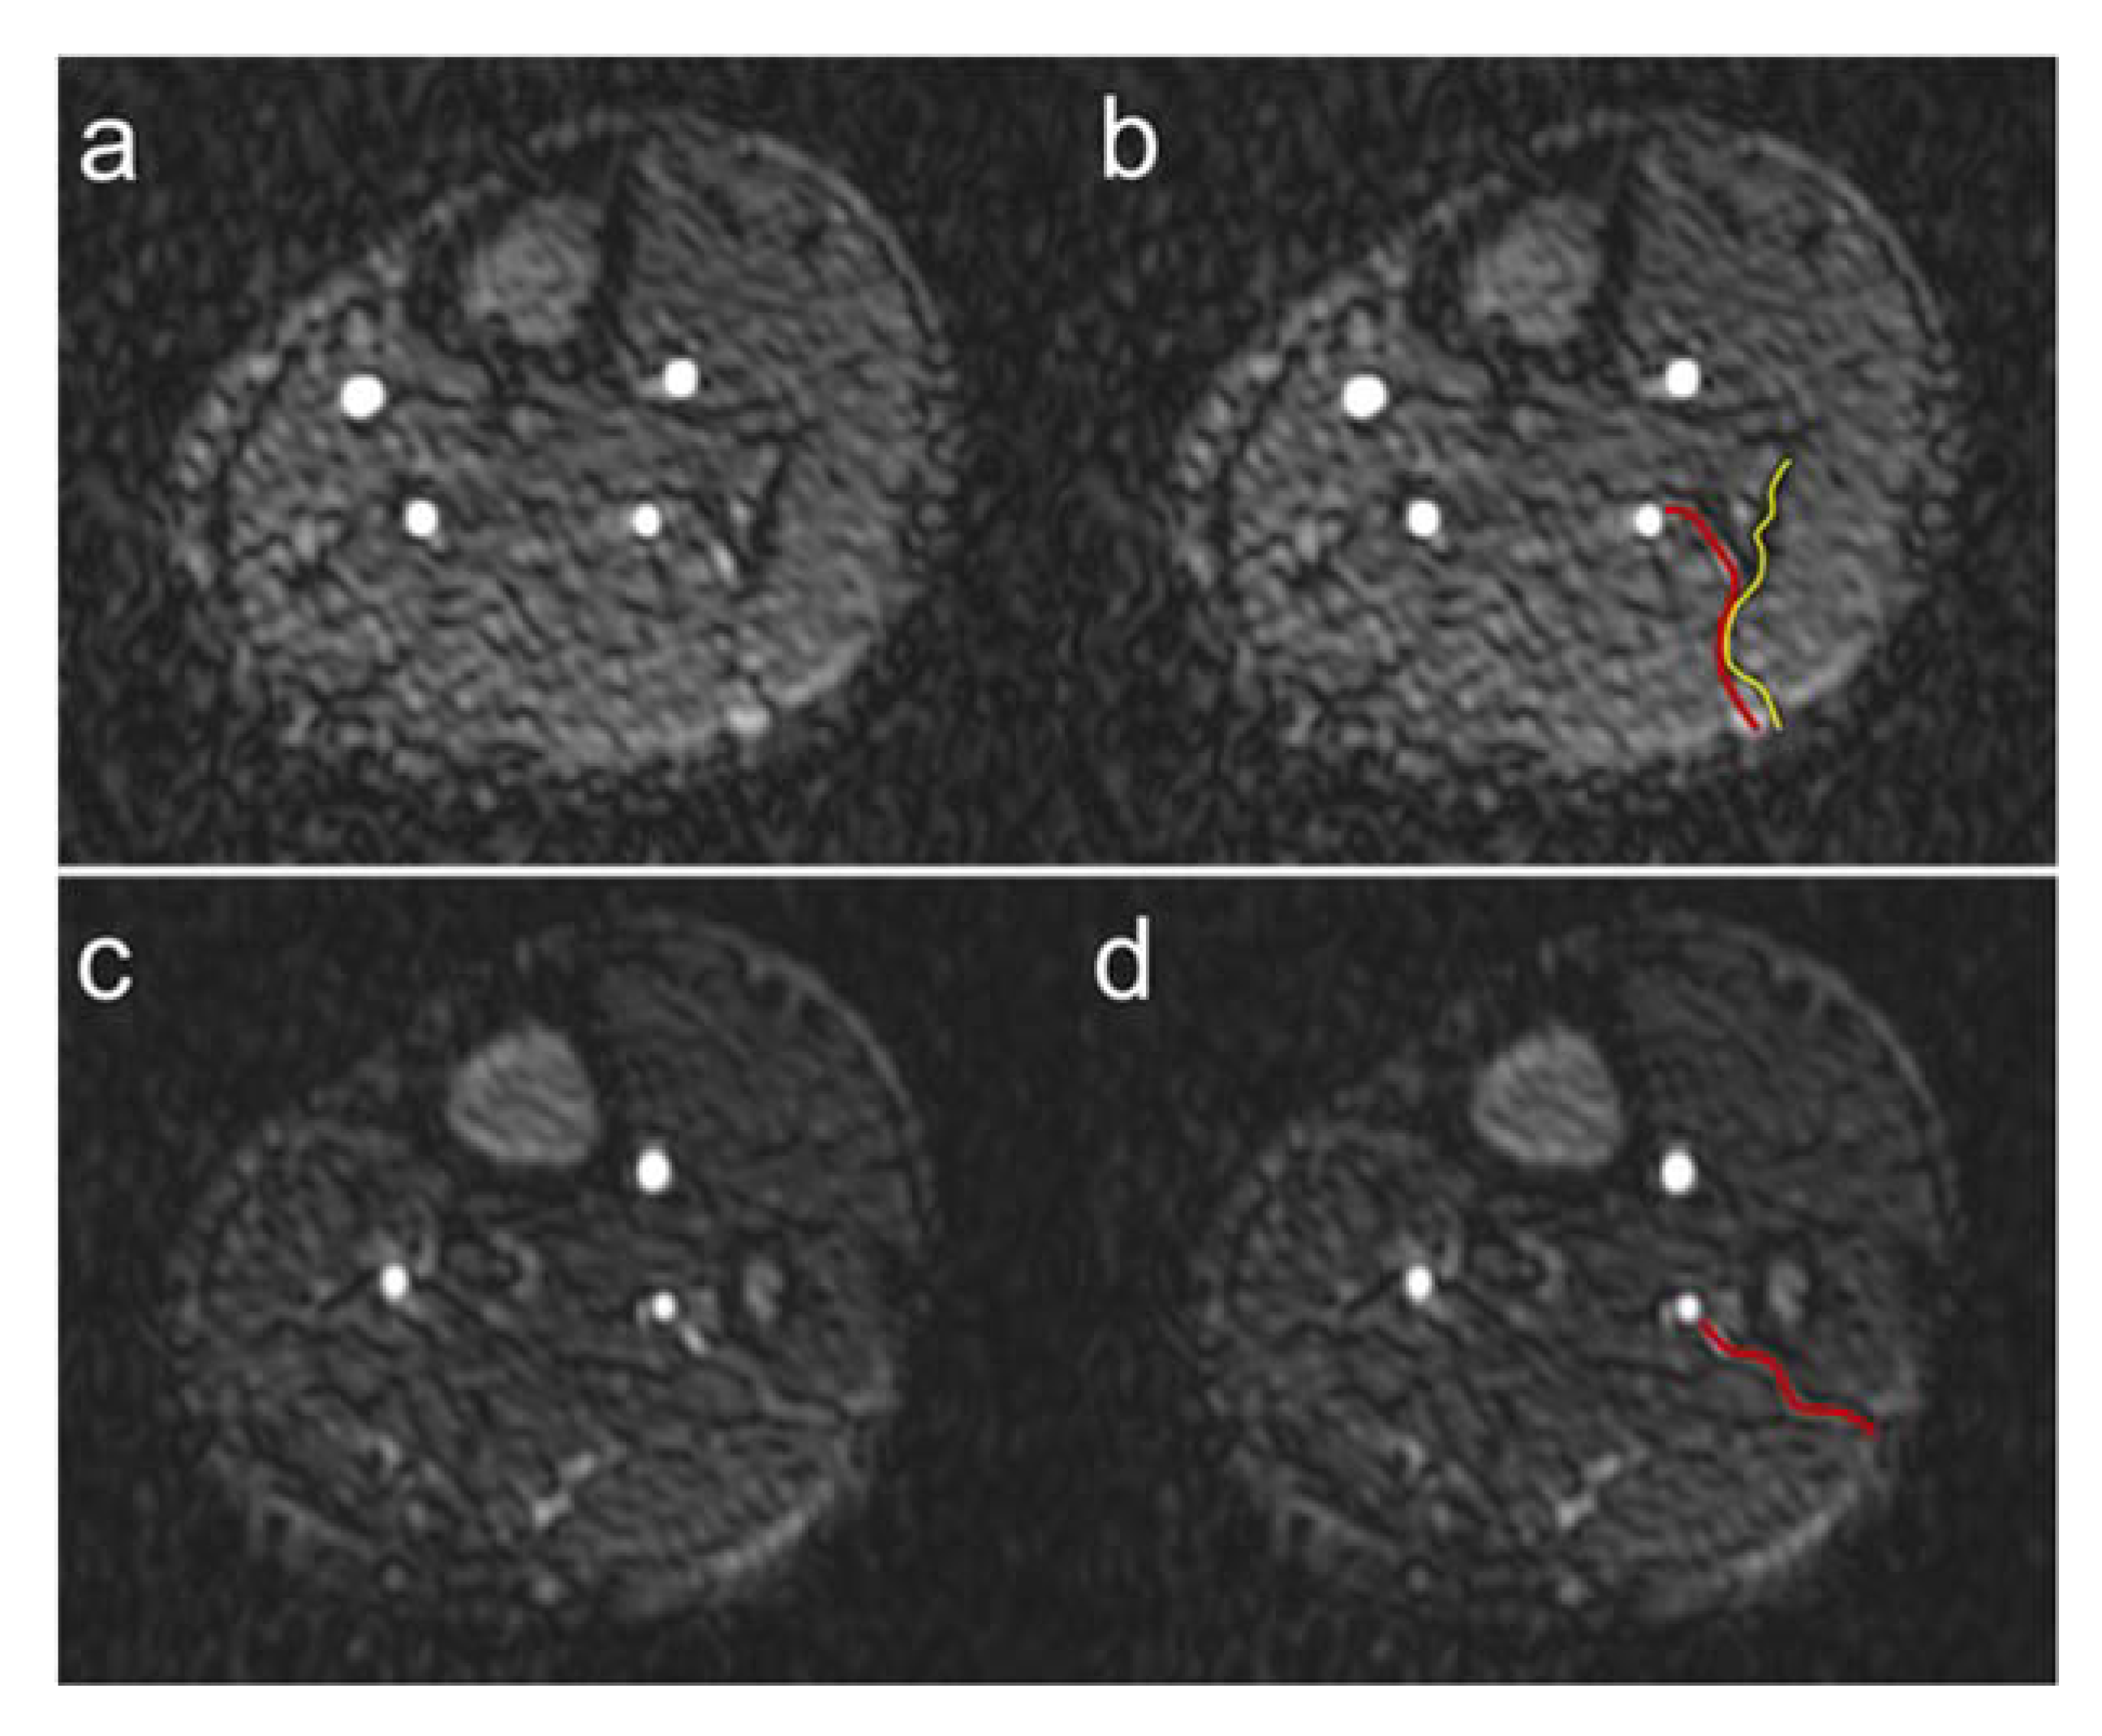

We were unable to detect fibular perforators in a total of 11 patient legs. In 4 of these 11 legs, fibular grafting was performed without subsequent graft failure, although the perforators were not visible. For this reason, we hypothesize that despite the excellent image quality, the already very high spatial resolution, and the predominant absence of artifacts of QISS-MRA, not all anatomically present fibular perforators, especially very small ones, can be detected. In the future, the use of even higher spatial resolution QISS-MRA pulse sequences, e.g., at 3T MRI, would be useful in this regard. QISS-MRA can distinguish between purely septocutaneous, purely musculocutaneous, and between fibular perforators, which mainly run within the septum and have a short course in muscle [6]. The typical course of the purely septocutaneous fibular perforators in the posterolateral intermuscular septum could be visualized by QISS-MRA (Figure 8).

Figure 8.

Course of fibular perforators. Exemplary course of a septocutaneous fibular perforator in the posterolateral intermuscular septum (a) in a 62-year-old male patient. The red line in panel (b) shows the course of the perforator, the yellow line the posterolateral intermuscular septum. Exemplary course of a septocutaneous fibular perforator to the cutis (c) in a 49-year-old male patient. The red line in panel (d) shows the course of the perforator to the cutaneous level.

Although the purely septocutaneous perforators are preferred for fibular transplantation because they are easier to harvest and do not require muscle resection, all three forms of fibular perforators are candidates for transplantation. For this reason, we did not distinguish between the three different types of perforators in our work. As shown in Figure 8, QISS-MRA can be used to follow the course of the perforators to the cutis in many cases. When this is not the case, it is probably because the perforators, like all vessels, taper in the periphery and become too small to detect.